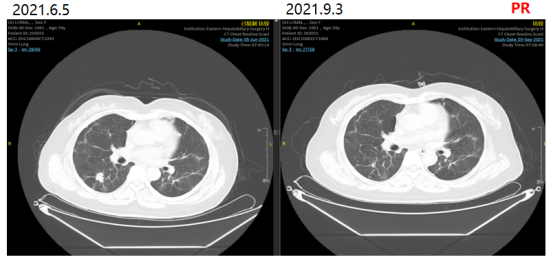

更换治疗方案为贝伐珠单抗+SIRI治疗。2021-06-05、2021-06-27、2021-07-20、2021-08-11分别予贝伐珠单抗500mg+伊立替康260mg 静滴+替吉奥60mg 2/日 q3w

治疗。

图2影像学复查结果

2021-09-04、2021-10-12、2021-11-3、2021-12-15再次原方案化疗4疗程。

2021-12-16评估疗效PR。